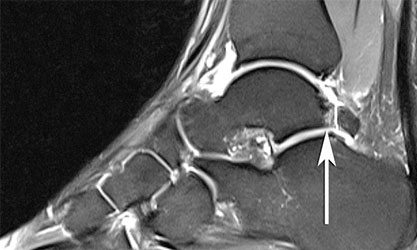

По МРТ и на рентгенограммах импинджмент голеностопного сустава.

Пациенту обязательно назначают рентгенограмму. На рентгенологическом снимке доктор легко увидит остеофиты – костные разрастания, появившиеся из-за воспалительного процесса. Дополнительно выполняется снимок в стрессовом положении. На нем доктор определит, есть ли соударение костей.

МРТ для диагностики недуга не является обязательным исследованием. Его выполнение рекомендуется, если необходимо провести дифференциальную диагностику с другими патологиями либо в начальных стадиях патологии.